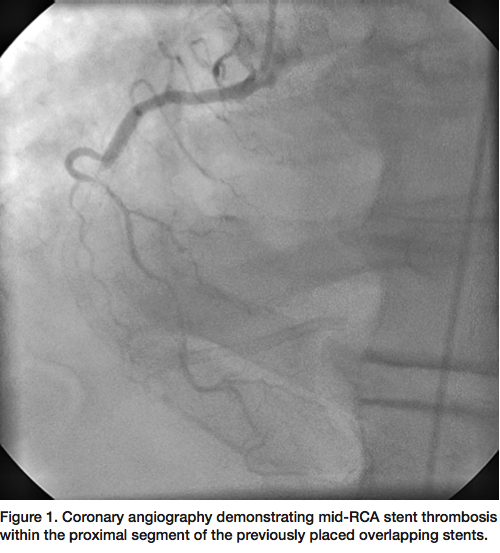

A 58-year-old male with known coronary artery disease and prior PCI of the right coronary artery (RCA) with multiple overlapping drug-eluting stents, presented with acute ST-segment elevation myocardial infarction (STEMI). Physical examination was unremarkable and laboratory analysis confirmed recent MI with troponin of 1.14. Electrocardiogram revealed acute ST-segment elevations in the inferior leads and reciprocal changes in the anterior leads. Coronary angiography revealed mid RCA stent thrombosis within the proximal segment of the previously placed stents (Figure 1).

A 6 French JR4 guide was used to engage the RCA. A Prowater wire (Asahi Intecc) was initially advanced but unable to cross the lesion. A PT Graphix wire (Boston Scientific) was then advanced with the use of an Apex 1.5 mm over-the-wire balloon (Boston Scientific) for support to cross the occluded segment into the distal RCA. Due to the degree of thrombus burden, laser atherectomy was performed (Figure 2) using a 0.9 mm ELCA catheter (Spectranetics) with no improvement in flow. Intravascular ultrasound (IVUS) of the entire stented

segment revealed an under-expanded stent with a reference vessel size of 4 mm. An NC Sprinter 4.0 mm balloon (Medtronic) was used to further dilate the stented segment, but with no improvement in flow. A ClearWay 1.0 x 10 mm perfusion balloon (Atrium) was then used to deliver intracoronary nitroglycerin, adenosine, and eptifibatide (Figure 3), with still no distal flow. Finally, the ClearWay balloon was used to deliver intracoronary tPA (2 mg bolus) with significant improvement in flow after 5 minutes of dwell time. Final angiogram revealed brisk TIMI-3 flow through the stented segment with excellent angiographic result (Figure 4).